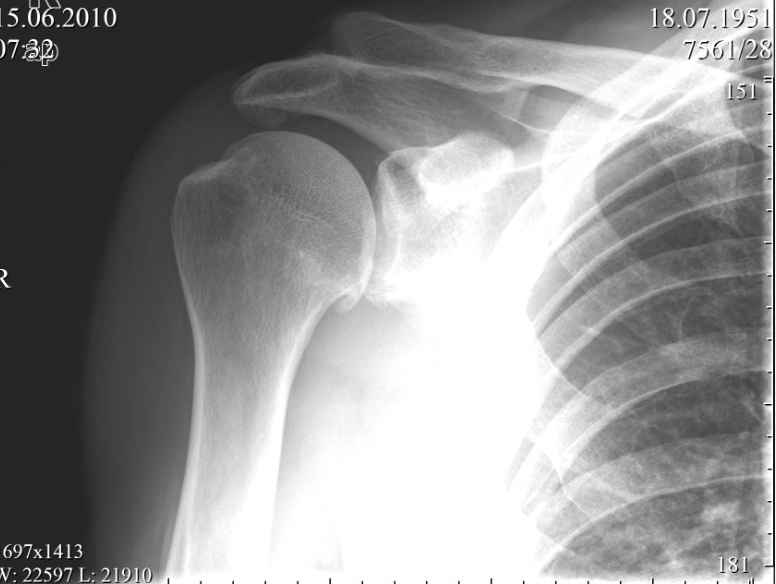

Пациент, мужчина, 59 лет обратился в июне с жалобами на умеренные периодические боли и хруст в

области правого плечевого сустава. В анамнезе, 1,5 года назад упал, ударился задней

поверхностью локтевого сустава, при отведенной правой руки в плечевом суставе и согнутом в

локтевом. Обратился за мед. помощью, по месту жительства, сказали, что ничего страшного,

повесили травмированную конечность на косынку. Тогда, в июне 2010года, когда я впервые

увидел пациента, он щадил руку, было ограничение объема движений в правом плечевом суставе.

Потому я предложил заняться лечебной физкультурой а потом посмотреть достигнутый

результат. Сегодня в пациента восстановлен полный объем движений в правом плечевом

суставе, боли сохраняются, но не такие выраженные, как раньше. Но при движении правой рукой

стоит ТАКОЙ хруст, что слышен на расстоянии. Пальпаторно, при движении правой

рукой,ощущается подвижность в акромиально-ключичном сочленении, и боли при отведении в

правом плече более 120 градусов. Пациента не устраивает нынешние положение дел с его плечом.

Хочет более радикального лечения. Я подумывая об операции, но побаиваюсь за результат.

Нужно иссечь рубцы, низвести акромиальный конец ключицы (а она будет "пружинить")и

фиксировать крючковидной пластиной к акромиону, не исключается выполнение

акромионопластики. Удержит ли пластина и удержатся ли взаимоотношения в

акромиально-ключичном сочленении, после удаления пластины? Тут вспомнился разговор с

профессором Джолдасом Кулджановым, о необходимости восстановления

клювовидно-ключичной связки. Хотелось бы освежить этот разговор в своей памяти и попросить

профессора найти время и рассказать еще раз о целесообразности и технике восстановления

клювовидно-ключичной связки, ну выслушать мнение коллег по Ортофоруму. С уважением